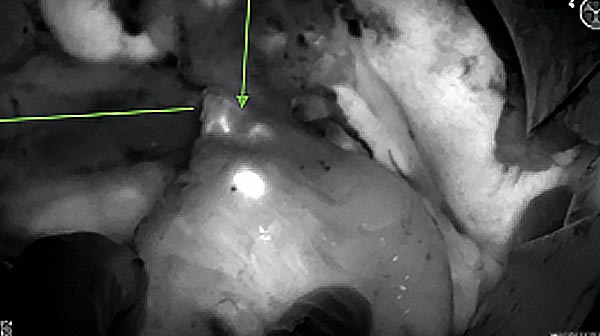

Intraoperative imaging panitumumab-IRDye800 (fluorescence)

Primary tumor prior to resection

Wound bed post re-resection of tumor

Fluorescence imaging of the tumor was performed prior to resection and after resection to “check” the wound bed. In the upper row the tumor is clearly visible with fluorescence and in the bottom row you can see that the wound bed is empty – there is no suspicious fluorescence left. The middle column of tiles show the fluorescence signal in black and white where the “white” represents the tumor and the black the background (= no fluorescence signal). The right column of tiles shows the overlay of the brightfield photo (in greyscale) and the fluorescence (red-yellow-blue heatmap). This image provides anatomical context to the surgeon – the surgeon can see where is the fluorescence located with regard to the tumor area.